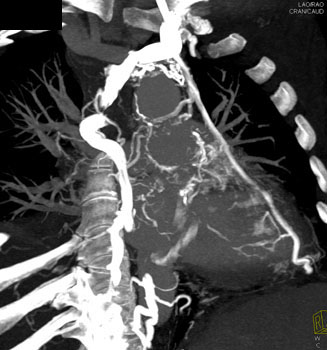

Question 18: In this patient with increasing dyspnea what is the best overall diagnosis?